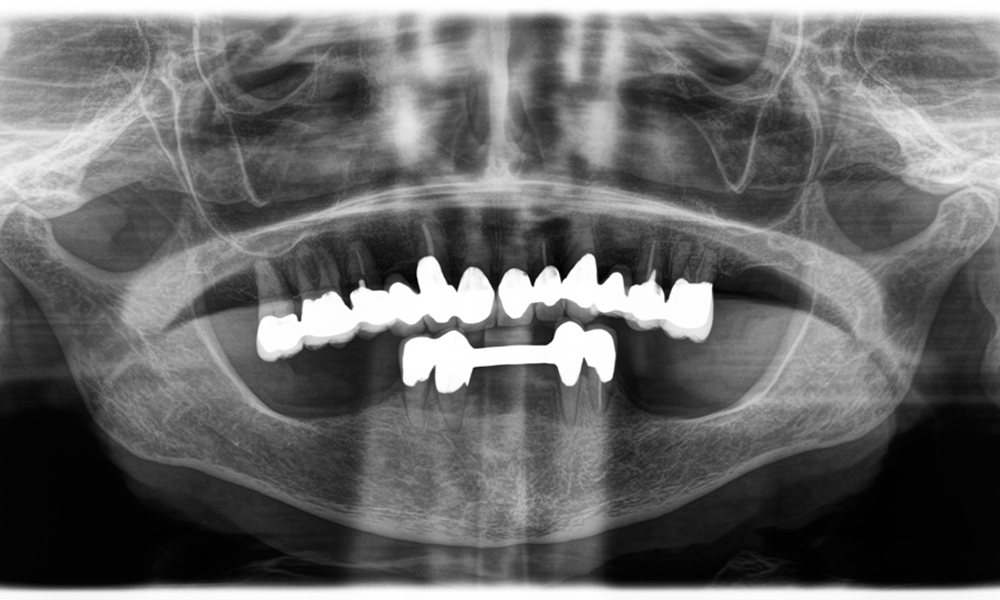

Рентгенова снимка на челюстта на 81-годишна пациентка.

Фигура 1: Естетична рехабилитация на металокерамични корони: Пълно отстраняване и подмяна на 40-годишни металокерамични корони за подобряване на естетиката при 81-годишна пациентка.